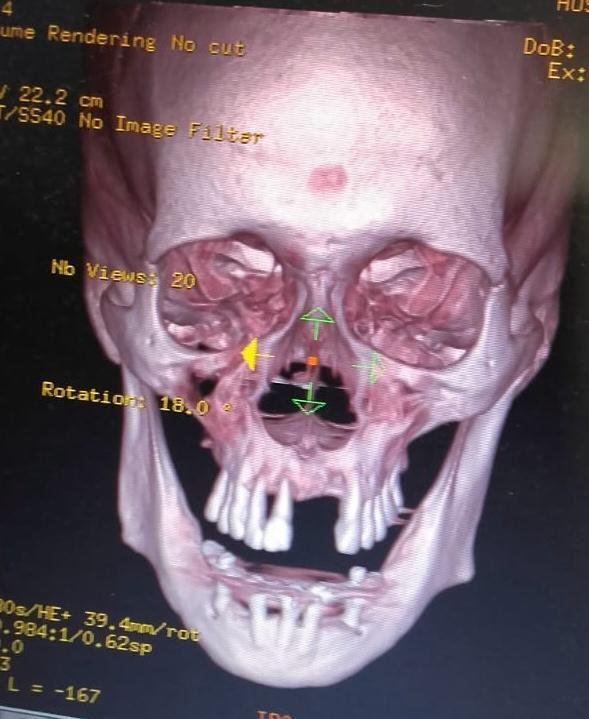

A avaliação por tomografia computadorizada, com ênfase na reformatação oblíqua em 3D, revelou a presença de foco infeccioso odontogênico com comprometimento ósseo significativo, extensão para estruturas adjacentes e potencial comunicação com seios paranasais — achados que não seriam plenamente identificados por métodos radiográficos convencionais.

Tomografia Computadorizada e Reformatação Oblíqua em 3D: Um Diferencial Diagnóstico

Embora ainda subutilizada pela Odontologia no ambiente hospitalar, a tomografia computadorizada representa um recurso diagnóstico de alto valor. A reformatação oblíqua em 3D possibilita:

- Avaliação precisa da extensão de lesões infecciosas

- Identificação de comprometimento ósseo profundo

- Planejamento cirúrgico mais seguro

- Comunicação efetiva com a equipe médica

O domínio dessa ferramenta amplia significativamente a capacidade diagnóstica do cirurgião-dentista hospitalar e fortalece sua atuação dentro da equipe multiprofissional.